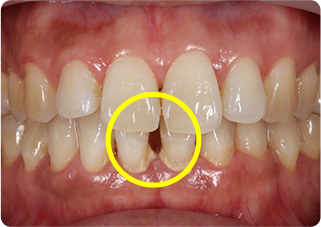

上唇小帯切除症例

術前

術後

| 主訴 | 上の前歯のすきっ歯が気になる |

|---|---|

| 治療期間/回数 | 1ヵ月、3回 |

| 価格(税込) | 保険適応 |

| リスク・副作用 | 出血、術後疼痛の可能性 |

| ポイント | 上唇小帯の付着異常により、正中離開が起きていた。上唇小帯を電気メスで切除した結果、歯を正中に寄せることが出来た。 |